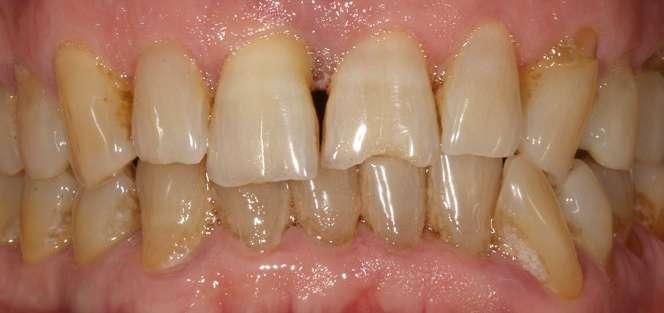

Caso clínico

Presentamos el caso de un paciente masculino de 61 años de edad, bruxista, con evidentes desgastes en toda la dentición y cracks de esmalte que pueden observarse en las fotografías iniciales de la primera visita (figuras 1 y 2). En las fotografías

Figuras 1 y 2. Imágenes intraorales de la primera visita donde se hacen evidentes diferentes desgastes en los dientes anteriores y a mayor detalle crakcs en el esmalte, así como lesiones por abfracción en los cuellos de los dientes de los premolares y caninos superiores.

laterales se ponen de manifiesto aún más varias lesiones de esmalte que indican la parafunción en el paciente, unido a los desgastes excesivos en varias zonas (figuras 3 y 4). El paciente acude por dolor y movilidad en la pieza 11, que se ha incrementado en los últimos días, además de sensación de “diente crecido” que como podemos ver en las fotografías iniciales es real, ya que el diente se encuentra ligeramente extruido en relación con el contralateral. Estos signos parecen indicarnos una fractura o fisura. En la fotografía oclusal, podemos observar el desplazamiento del diente debido a la movilidad (figura 5). Posteriormente se realiza un sondaje positivo de la pieza, que lleva a 11 mm por lo que se confirma la sospecha de fractura y se procede a la exodoncia del diente, realizándose una regeneración posterior del alveolo con PRGF-Endoret y

Figuras 3 y 4. Fotografías laterales donde se evidencian los cracks de esmalte en varios dientes y los desgastes excesivos en varios puntos. En estas imágenes se hacen más evidentes las lesiones por abfracción.

Figura 5. Toma oclusal donde se hace evidente el desplazamiento del diente por el que consulta el paciente, que parece indicarnos una gran pérdida ósea a ese nivel.